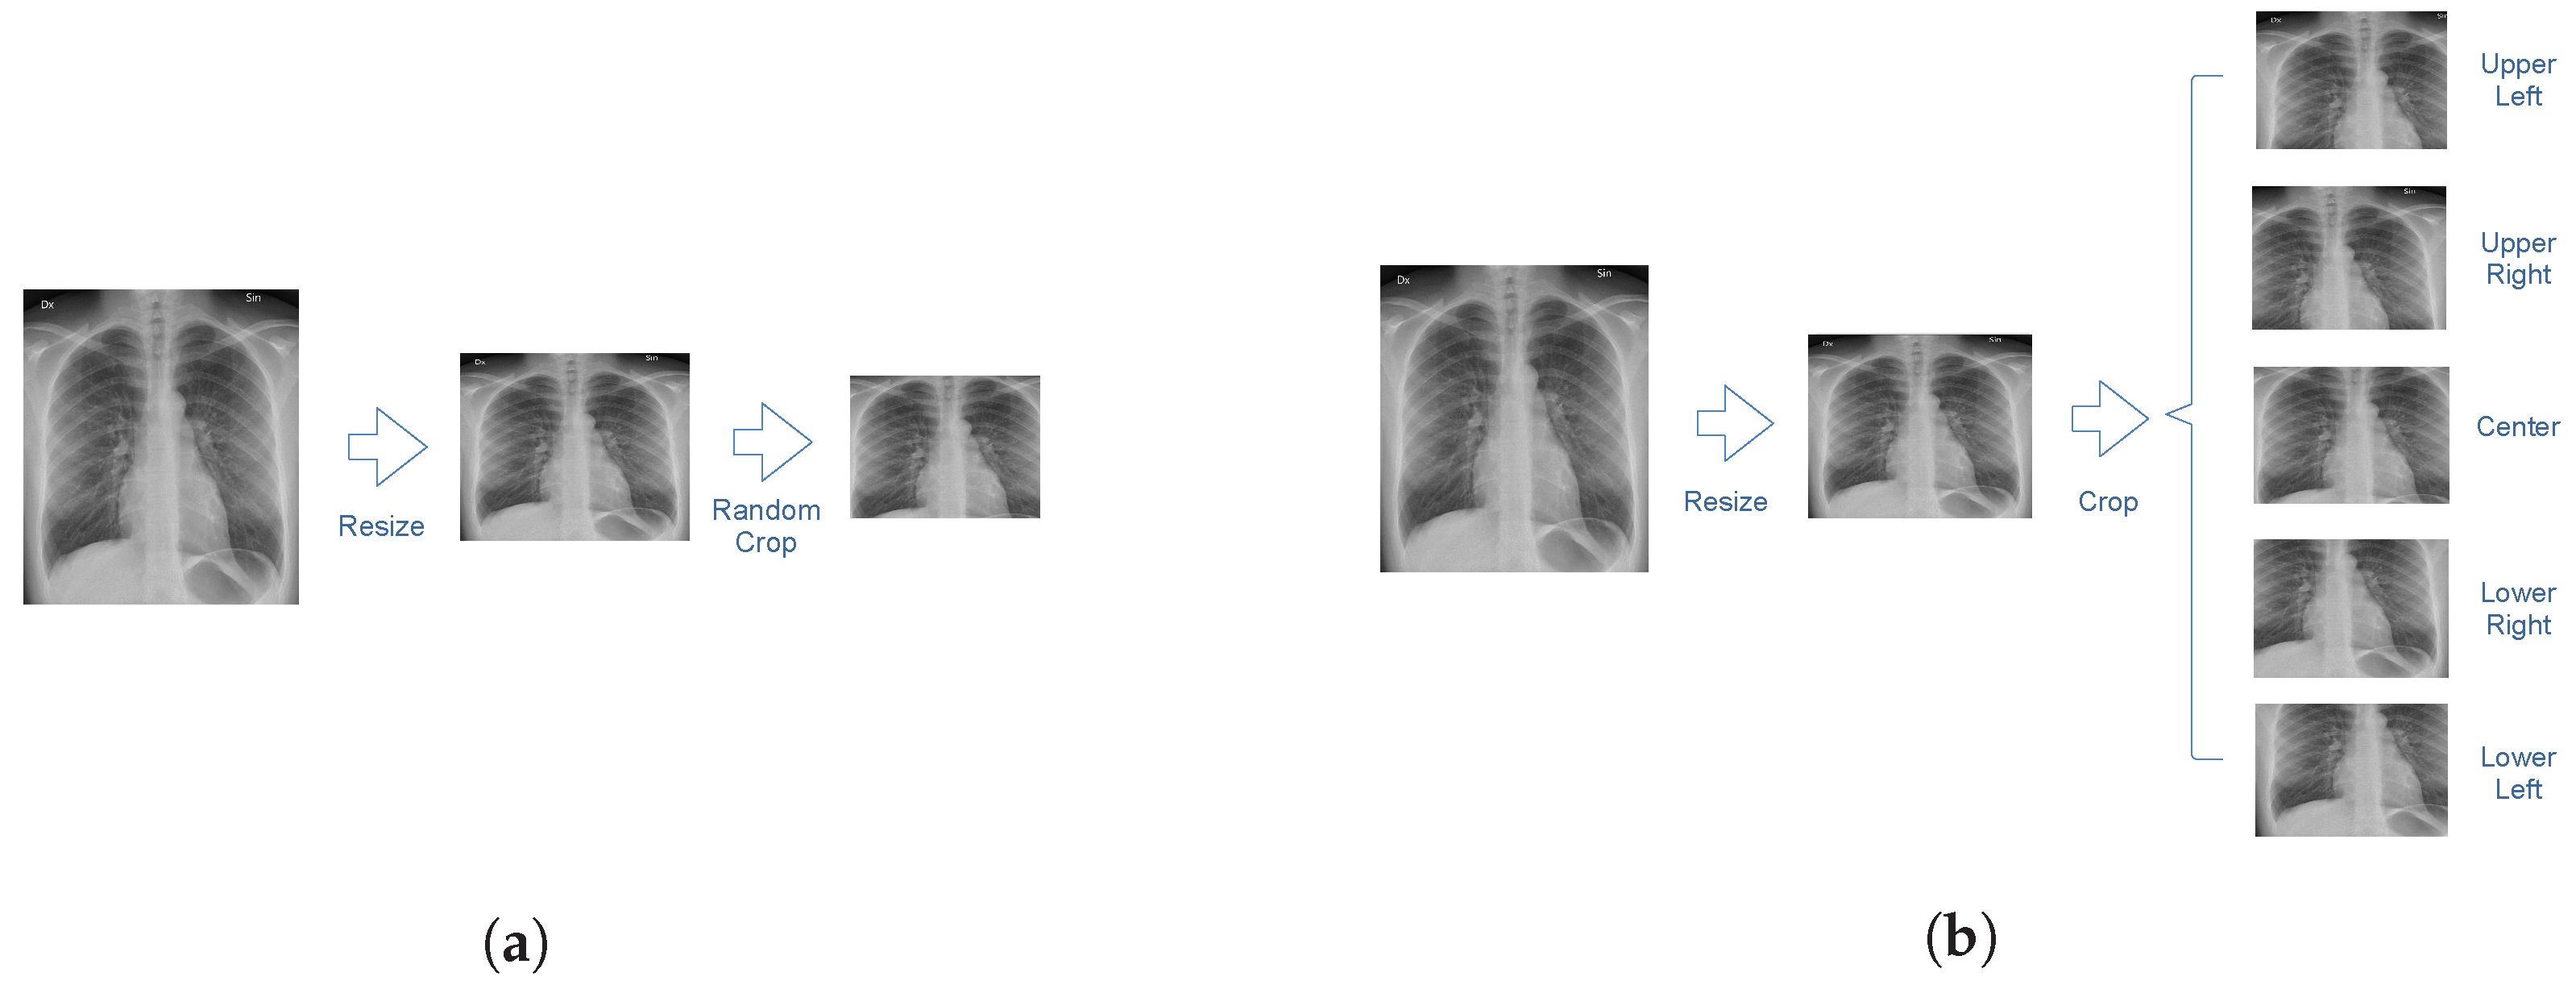

An illustration of the image preprocessing procedure is shown in Figure 2. The size of each image is 2500 by 2100 pixels. In order to reduce computational costs, each chest radiograph was resized to a 256 by 256-pixel image. Images in the training dataset were cropped to 224 by 224 pixels at a random position. Images in the testing dataset were cropped at the four corners and the center. Predictions were obtained for each crop independently and averaged to obtain a final prediction for the entire image.

Figure 2.

An illustration of the resizing and cropping procedure. (a) Images in the training dataset were resized and cropped at a random position. (b) Images in the test dataset were resized and cropped at the corners and the center.